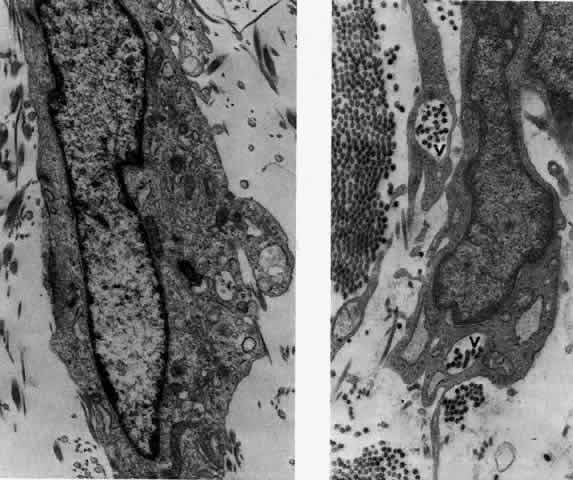

What is clinically represented solely by inflammation and edema is histopathologically a granulomatous lesion of the sclera, the center of which consists largely of plasma cells, lymphocytes, and mast cells (Figs. 21 through 23). Foster and colleagues have identified the cellular subsets and glycoproteins in both necrotizing and non-necrotizing scleritis.22 This shows an active T-cell inflammatory response with a high CD4/CD8 ratio and increased HLA/DR and CD14, indicating a macrophage-induced response that would lead to granuloma formation. Remote from the granuloma, the fibrocytes of the sclera become activated, the proteoglycan adjacent to them becomes altered, and the collagen fibrils of the sclera become unraveled (Figs. 23 and 24). These changes appear to take place prior to the invasion of the stroma by cells of the granuloma.20 The vessels in and around the necrotic area show medial necrosis and perivascular cuffing with lymphocytes, and endothelial swelling with microvascular occlusion. Ninety-six percent of the specimens examined by Foster and associates show a microangiopathy characterized by a neutrophil infiltrate in and around the vessel wall.22–23 This is most obvious at the center of the lesion where there may be occlusion of the vessel, thrombosis, or even aneurysm formation (Fig. 25). From these pathologic investigations, clinical observations, animal experiments, and the results of fluorescein angiography, it would appear that the scleral inflammation is initiated either by trauma (be it accidental or surgical)23–25 or by bacterial or viral infection. If circulating immune complexes are present because of the poor blood flow, they become precipitated in and around the vessel walls in the area of inflammation. In other patients, a persistence of tissue damage will lead to autoimmunization. Damage to the endothelial cells of the microvasculature leads to changes within the vessels detectable on angiography and to catabolic changes in the surrounding tissues. These changes, in turn, allow the granulomatous response that is seen in histopathologic sections, the first detectable change being in the scleral fibrocytes and the proteoglycan and collagen remote from the site of cellular infiltration.

Fig. 21. Advancing edge of a granulomatous reaction. Scleral fibers are split and separated by edema and then disrupted when invaded by the granuloma

Fig. 22. Electron micrograph of an area of active scleritis showing the plasma cell infiltrate suggestive of an immune response. Note aggregated plasma cells, with the characteristic whorled rough endoplasmic reticulum, in the process of degeneration, releasing organelles and nuclear debris into the extracellular matrix. (Uranyl acetate and lead citrate. X3000) (Courtesy of Dr. R. Tripathi)

Fig. 23. Electron micrographs of scleral stroma at the periphery of an area of ulceration in a patient with necrotizing scleritis. The left shows an active fibroblastic cell, and the right shows collagen fibrils within intracellular vacuoles (V) in the fibroblastic cell. (Left X15,375; right X15,375) (Watson PG, Young RD: Changes at the periphery of a lesion necrotizing scleritis: Anterior segment fluorescein angiography correlated with electron microscopy. Br J Ophthalmol 68:781–789, 1984)

Fig. 24. Electron micrograph of scleral stroma at the periphery of an ulcer in necrotizing scleritis (same patient as in Figure 23) showing swelling and unraveling of collagen fibrils (arrows) in longitudinal section (X29,270) and in transverse section (inset, X44,000). Fibrils of all diameters are affected. (Watson PG, Young RD: Changes at the periphery of a lesion necrotizing scleritis: Anterior segment fluorescein angiography correlated with electron microscopy. Br J Ophthalmol 69:656–663, 1985)